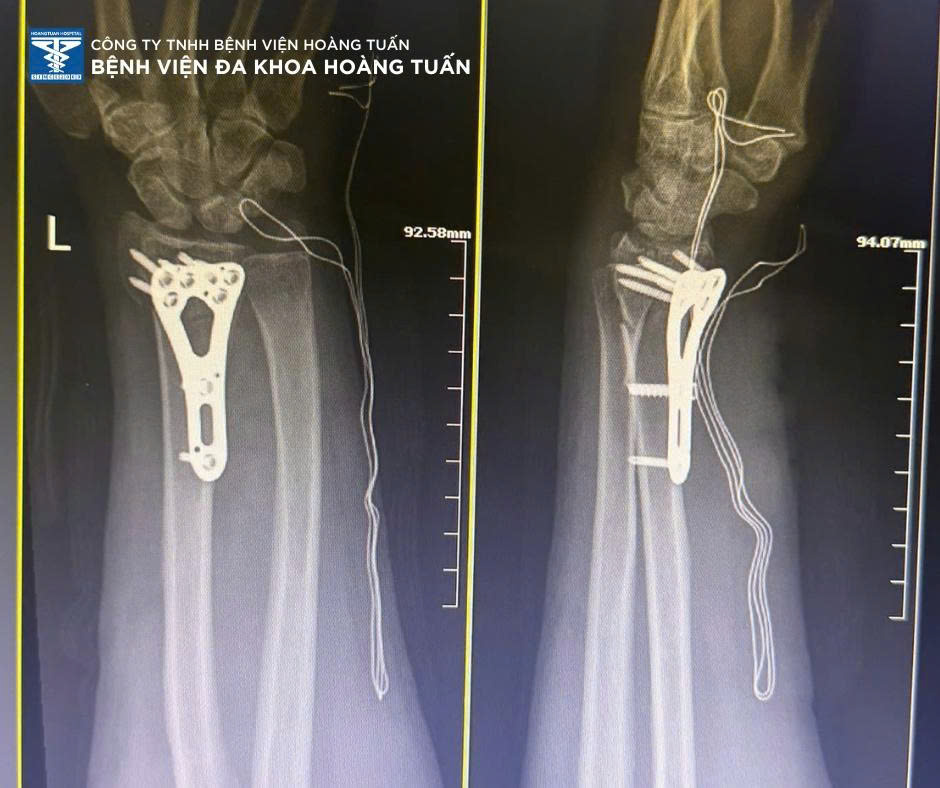

Một trường hợp khác tương tự, bệnh nhân nữ 57 tuổi, tai nạn sinh hoạt tại nhà sưng đau nhiều vùng cẳng tay phải, được người nhà đưa đến khám tại Bệnh viện Đa khoa Hoàng Tuấn.

Sau thăm khám và chụp X-quang kiểm tra, BSCKI. Vũ Quốc Dũng – Khoa Ngoại CTCH Bệnh viện Đa khoa Hoàng Tuấn nhận định bệnh nhân đã gãy đầu dưới 2 xương cẳng tay phải, cần phẫu thuật kết hợp xương điều trị sớm. Ekip phẫu thuật Bệnh viện Đa khoa Hoàng Tuấn nhanh chóng chuẩn bị bệnh nhân và tiến hành thực hiện sớm. Sau phẫu thuật bệnh nhân vận động nhẹ, giảm sưng đau, đang trong thời gian phục hồi vận động và theo dõi tiến triển.